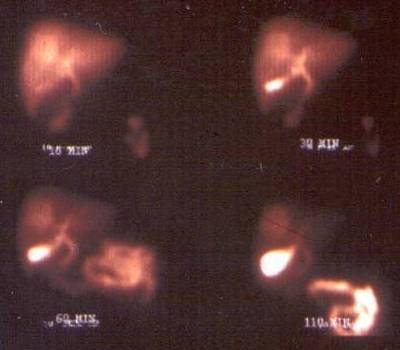

14.1.1.8. Nuclear medicine

The role of colloid liver scintigraphy (intravenously administrated 99mTc-marked radiocolloid) has been clearly dropped in the past 15-20 years because its spatial resolution can not reach the modern applicable resolution of US and multidetector CT devices.

The blood-pool scintrigraphy of 99mTc-marked red blood cells helps by planar detection in the non-invasive diagnostic imaging in case of larger and superficial located cavernous hemangiomas (6-9 cm). The 99mTc-marked red blood cell (RBC) SPECT (Figure 10) can also detect the smaller and deeplier located (2-3 cm large) hemangiomas as well.

Figure 10: SPECT of the liver

In case of the clinically suspicious liver or subphrenic abscess – if the US and CT findings are doubtful – leukocyte scintigraphy may be also helpful in the diagnosis.